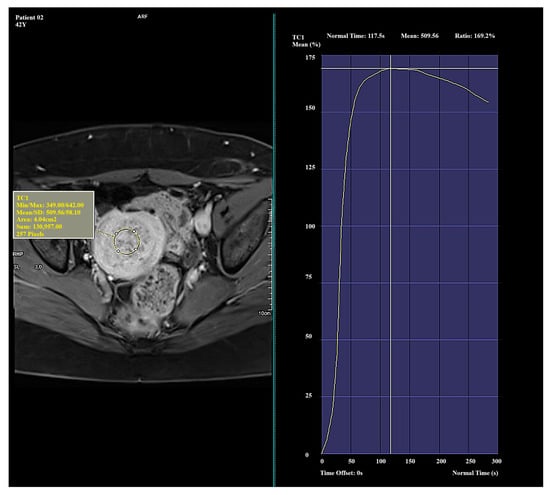

In Type I, the average Ratio was 156.96 ± 20.94 (Me = 156.89), the average TTP was 127.04 ± 42.05 (Me = 133.76), and the average Mean was 538.98 ± 55.51 (Me = 538.35). In Type II, the average Ratio was 122.04 ± 25.57 (Me = 113.85), the average TTP was 260.31 ± 33.91 (Me = 276.99), and the average Mean was 452.77 ± 8.38 (Me = 451.75). In Type III, the average Ratio was 37.60 ± 44.98 (Me = 33.41), the average TTP was 218.24 ± 89.10 (Me = 250.74), and the average Mean was 235.84 ± 111.76 (Me = 252.89). The mean values of perfusion parameters for each Funaki classification type are shown in Table 3.

In this study, a decrease in both Ratio and Mean values was observed from Type I to Type III, indicating a gradual decline in vascularization intensity. This trend reflects a progression from highly vascularized, biologically active myomas (Type I) to poorly vascularized lesions (Type III). The TTP value increased from Type I to Type II, which may suggest slower contrast enhancement dynamics in less vascularized myomas. In contrast, Type III exhibited a lower TTP value despite its low overall enhancement, possibly due to a limited dynamic enhancement range and the absence of a well-defined signal peak.

Significant and distinct differences in perfusion parameters were observed across the types. Type I lesions demonstrated strong and rapid enhancement and are likely the most biologically active. Type II lesions represented an intermediate category, showing clinical variability. Type III lesions—though rare in this study—displayed very low enhancement and signal intensity, which may correspond to fibrotic or ischemic changes. Due to the small number of Type III cases (n = 4), observations related to this group should be interpreted with caution and validated in a larger cohort. Representative enhancement curves for each Funaki classification type are illustrated in Figure 1, Figure 2 and Figure 3.

Figure 2. Example of amplification curve for Funaki Type II.